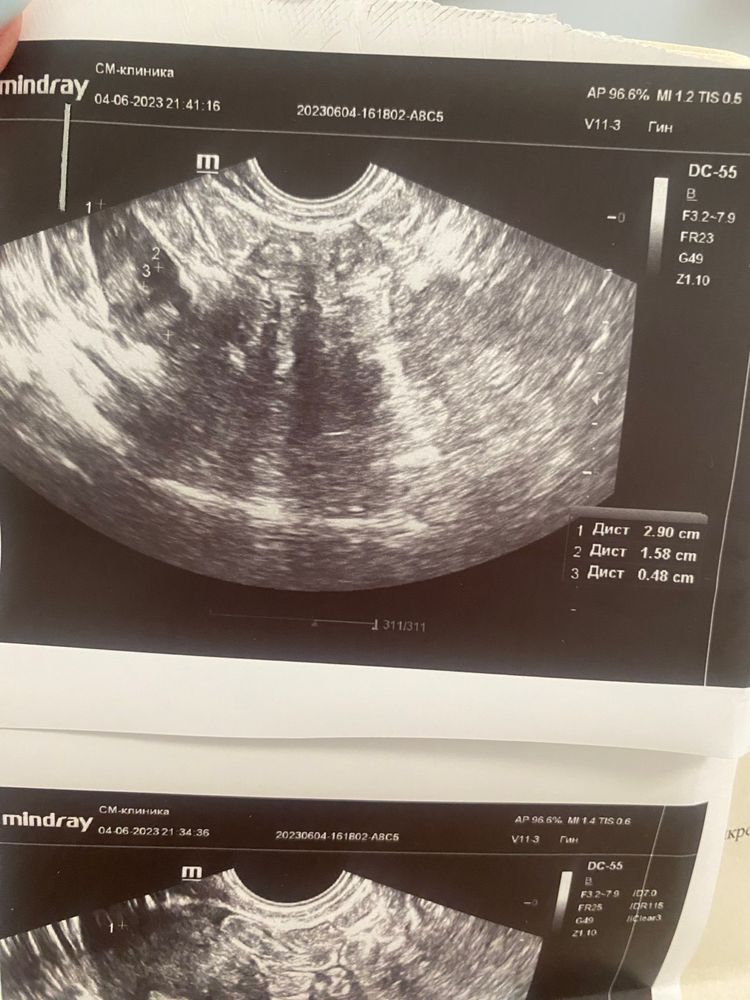

УЗИ удалось сделать, врач узи (не гинеколог) сказала, что желтого тела нигде нет. Овуляции не было и не предвидится уже (21 день цикла).

Я скинула гинекологу снимки узи и заключение, она написала: «По эндометрию как будто бы овуляция была. Если будет возможность, на этой неделе сдайте кровь на прогестерон.»

В общем, сдала я кровь на прогестерон, скинула гинекологу и она сказала, что овуляция была. Я спросила - её просто не увидели на УЗИ? Она сказала, что да.